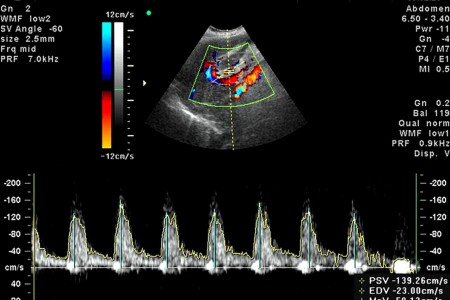

Доплер – это одна из современных разновидностей УЗИ, которая проводится для диагностики кровеносных сосудов и кровотока при помощи анализа звуковых волн. Такой метод исследования позволяет максимально точно определить состояние потока крови при сужении шейных сосудов, что может привести к инсульту. При помоши доплера УЗИ проводится диагностика сосудов ног, которая может выявить наличие кровяных сгустков, приводящих к нарушению легочного кровотока. УЗИ с доплером назначают беременным для выявления нарушений кровотока  и состояния плода.

2. Двойное УЗИ доплера. Данный тип исследования проводится стандартным для УЗИ способом, в результате которого выявляются данные в виде изображения о состоянии сосудов и расположенных рядом органов. Помимо этого анализируются звуки, которые трансформируются в так называемую «доплерографию» для определения характера и скорости оттока крови.

3. Цветная доплерография. Стандартные результаты УЗИ выводятся в формате цветного изображения, на котором отображены кровеносные сосуды.Звуки и цвета формируют единую схему, которая демонстрирует данные о скорости оттока крови.

Результаты исследования: что является нормой, а что патологией?

Отсутствие тромбов и барьеров при оттоке крови, нормальные размеры вен – все это является нормой для здорового человека. У беременных важно зафиксировать нормальный отток крови для беспрепятственной подачи кислорода и необходимых веществ, поступающих к плоду.

При нарушении кровотока фиксируется разница между обеими конечностями пациента. В области, где обнаружено препятствие, можно будет услышать резкие звуки.

Любые виды препятствий, затрудняющих отток крови можно обнаружить при помощи доплер УЗИ. При этом скорость оттока крови будет заметно сокращена по сравнению с нормой.

При проведении двойного УЗИ доплера фиксируется нарушение регулярности оттока крови, что говорит о сужении или наличии барьеров кровеносного сосуда.

Цветное УЗИ доплера может быть обнаружено сужение кровеносного сосуда, его блок, а также аневризму.

При исследовании вен можно зафиксировать наличие кровавого сгустка. Это можно обнаружить при проведении теста Вальсальвы, при сжатии, и в случае, если отток крови не изменит свои показатели в ответ на дыхание. Обнаружить сгусток, блокирующий кровоток, также можно при цветном УЗИ доплера.